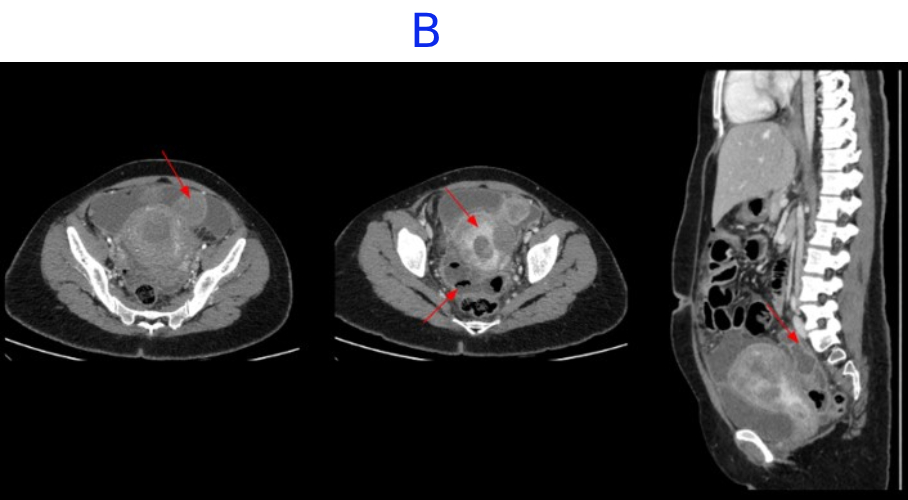

• C. CECT ABDOMEN AND PELVIS- DAY 7- STATUS POST EXPLORATORY LAPAROTOMY AND PERITONEAL LAVAGE

• D. Bulky uterus with a hypodense submucosal lesion protruding into the endometrial cavity from the fundus showing heterogeneous enhancement - infected vs infarcted fibroid. Abnormally enhancing endometrial lining with hypodense content within the endometrial cavity - possible endometritis with pyometra. Pelvic peritonitis with residual trace fluid in the pelvis. Interval resolution of pneumoperitoneum. Abdominal drains in situ.

• E. Bulky uterus with a hypodense submucosal lesion protruding into the endometrial cavity from the fundus showing heterogeneous enhancement - infected vs infarcted fibroid. Abnormally enhancing endometrial lining with hypodense content within the endometrial cavity - possible endometritis with pyometra. Left sided pyosalpinx.

• Bulky uterus with a hypodense submucosal lesion protruding into the endometrial cavity from the fundus showing heterogeneous enhancement - infected vs infarcted fibroid.

• Abnormally enhancing endometrial lining with hypodense content within the endometrial cavity - possible endometritis with pyometra

• Left sided hydro/pyosalpinx.